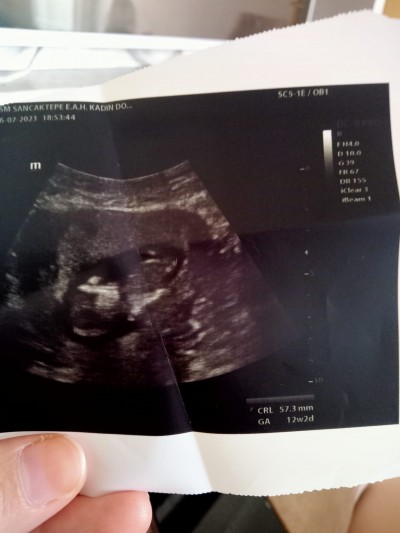

Burda 12 haftalık kızlar doktor tahmin yapmadı bacakları çok oynuyordu siz ne diyorsunuz daha ogrenemedim 14+1 şuan

image